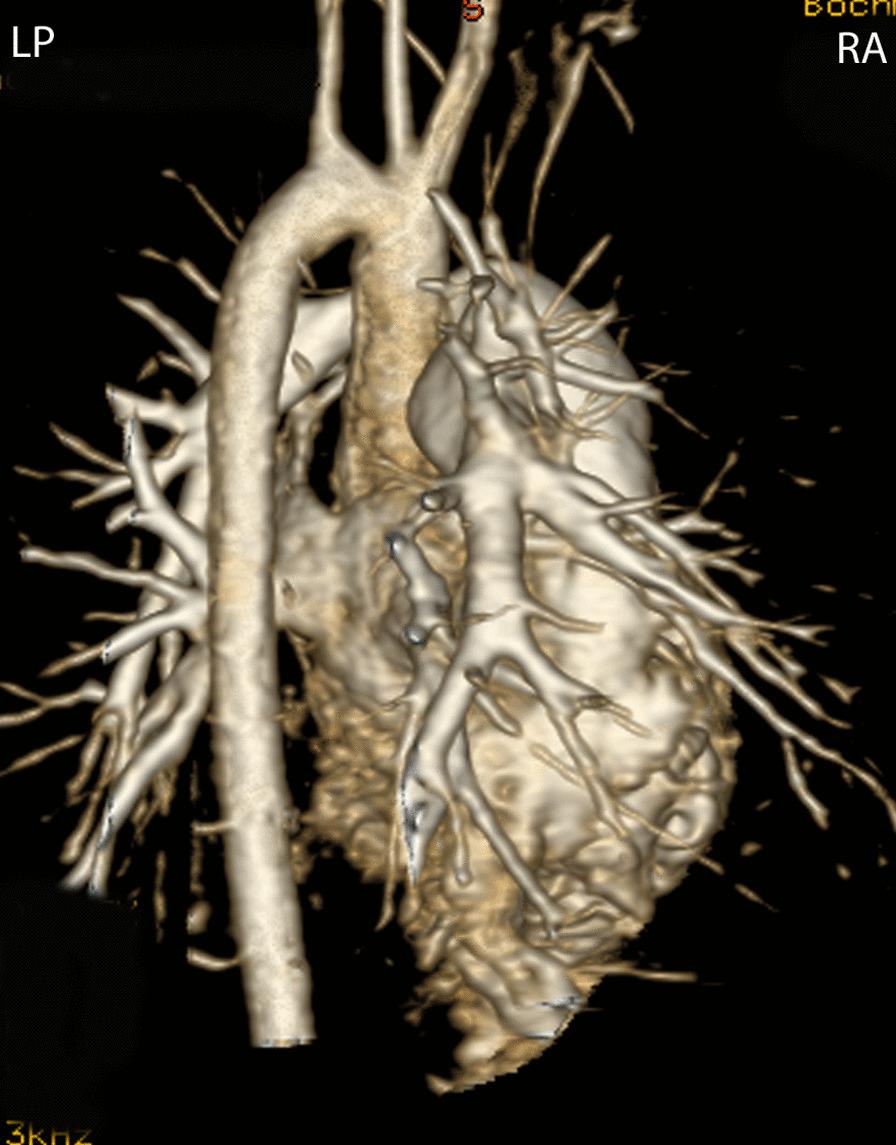

Cardiovascular magnetic resonance (CMR) has been utilized in the management and care of pediatric patients for nearly 40 years. It has evolved to become an invaluable tool in the assessment of the littlest of hearts for diagnosis, pre-interventional management and follow-up care. Although mentioned in a number of consensus and guidelines documents, an up-to-date, large, stand-alone guidance work for the use of CMR in pediatric congenital 36 and acquired 35 heart disease endorsed by numerous Societies involved in the care of these children is lacking. This guidelines document outlines the use of CMR in this patient population for a significant number of heart lesions in this age group and although admittedly, is not an exhaustive treatment, it does deal with an expansive list of many common clinical issues encountered in daily practice.

心血管磁共振(CMR)在儿科患者的管理和护理中已经应用了近 40 年。它已经发展成为评估最小的心脏的宝贵工具,用于诊断、介入前管理和随访。尽管在许多共识和指南文件中提到,但在儿科先天性心脏病和后天性心脏病领域,目前还缺乏一份由众多参与儿童护理的学会共同认可的、最新的、独立的、针对 CMR 使用的大型指南。本指南文件概述了 CMR 在该年龄段的许多心脏病变中的应用,尽管不能说是详尽的治疗方法,但它确实涉及了在日常实践中经常遇到的许多常见临床问题的广泛列表。